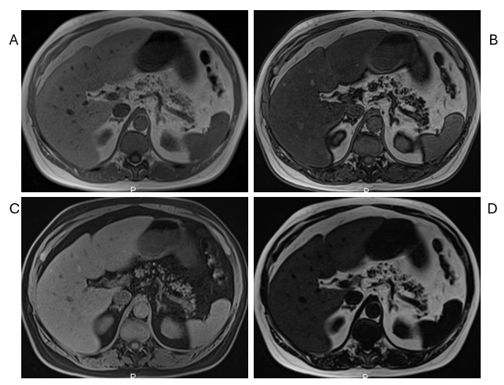

Figure 2 Severe fat infiltration. Axial T1 Dixon GRE: In-Phase (A), Out-of-Phase (B), Fat Sat (C), and Fat only (D) images. Severe pancreatic steatosis appears subjectively as the total fat content of the pancreas to be approximately 75% of the gland.